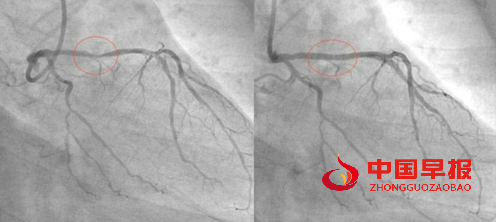

他是一位虔诚的回教徒,为了让更多的人受益,他把自己的经验放在网上分享,他的前后两张血管照片也放了在网上,在他的冠状动脉造影照片中,服用食疗之前与之后的分别连普通人也看得出来。